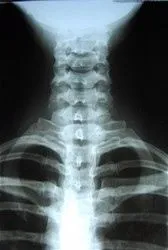

X-rays are often taken on most patients to give the doctor an inside look at what is going on with the bone structure of the entire spine and surrounding skeletal structure. From this x-ray, the doctor can tell your current spine angles as well as any potential further issues including the potential for additional information such as an MRI.